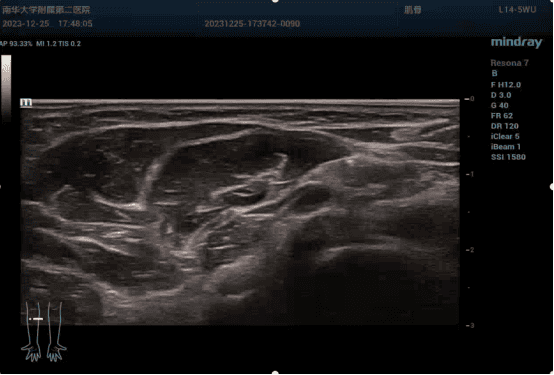

科室业务范围广泛,涵盖心脏(含心脏发泡试验、经食道超声心动图等)、外周血管、腹部、妇产(含输卵管造影、妇科肿瘤造影、盆底超声等)、浅表器官、肌骨(含肌骨超声引导、超声引导下神经PAP注射治疗、超声引导下皮瓣血管定位等)、小儿、重症超声、术中超声引导及介入超声诊断与治疗等领域。其中,肌骨超声、介入超声、超声造影、术中超声引导、盆底超声、胃十二指肠造影、经直肠肛管超声等新技术处于国内先进水平。

1、腹部亚专业组:腹部超声亚专业组是超声医学领域的重要分支,专注于腹部脏器及相关疾病的超声诊断与评估。专业范畴涵盖肝脏、胆囊、胰腺、脾脏、肾脏、输尿管、膀胱、前列腺等腹部脏器,以及腹腔、腹膜后等区域的疾病诊断。尤其在肝胆胰疾病、泌尿系统疾病及腹部占位性病变的诊断中具有显著优势。